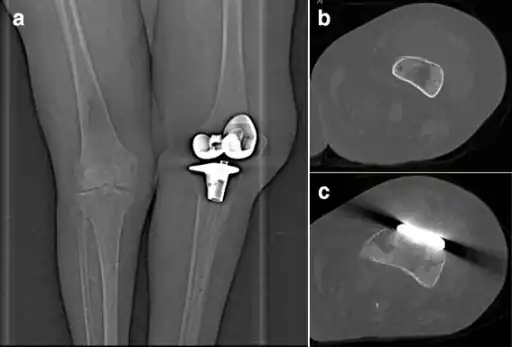

In humans, P. multocida is the most common cause of wound infections after dog or cat bites. The infection usually shows as soft tissue inflammation within 24 hours. High leukocyte and neutrophil counts are typically observed, leading to an inflammatory reaction at the infection site (generally a diffuse, localized cellulitis).[14] It can also infect other locales, such as the respiratory tract, and is known to cause regional lymphadenopathy (swelling of the lymph nodes). In more serious cases, a bacteremia can result, causing an osteomyelitis or endocarditis. Patients with a joint replacement (perhaps notably knee replacement) in place may, in particular, be at risk of secondary infection of that joint during an episode of P multocida cellulitis/bacteraemia. The bacteria may also cross the blood–brain barrier and cause meningitis.[7][15]